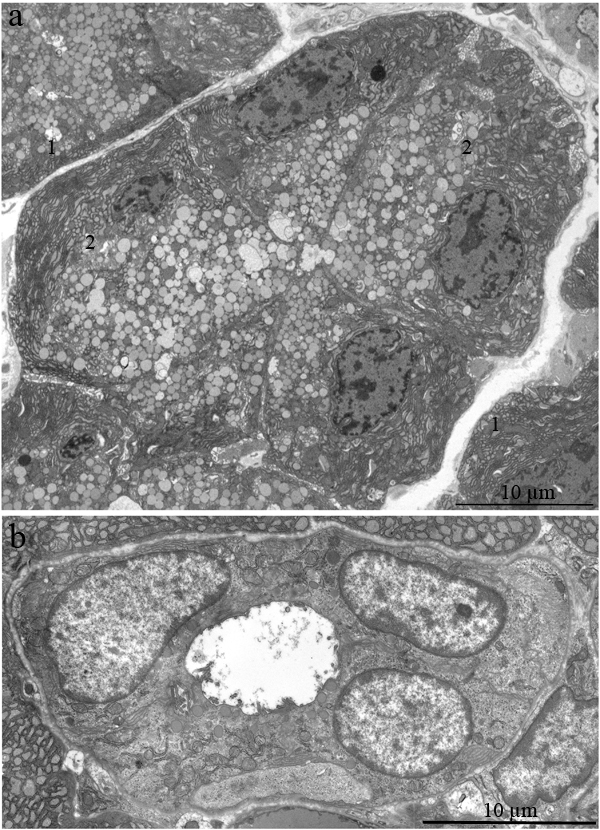

The ultrastructure of the lacrimal gland varied significantly with age. At 3 months of age, ultrastructure of acini and intercalary ducts conformed to the classical ultrastructural concepts of the lacrimal gland (Figure 1a, 1b). Figure 1a depicts the acinar cells, which were arranged in groups of 6-8 and formed acini that looked like a rosette with a clear center on a cross-section. Nuclei of the acinar cells were round and located near the basal membrane. The basal region of the cells was filled with the ER closely surrounding the nucleus (arrows “1” in Figure 1a). In the tight layers of the cytoplasm between the ER membranes, there were mitochondria with a small number of cristae and a light-gray matrix (Figure 2a). The apical region of the acinar cells was filled with many secretory vesicles with contents of varying electron density (arrows “2” in Figure 1a). In the literature, these structures are defined as secretory granules. We found that neighboring acinar cells in acini formed special connecting intercellular junction complexes involving desmosomes and mitochondria that were tightly adjacent to tonofilaments on the side of each contacting cell (Figure 3). In the duct cells, the cytoplasmic contents looked inconspicuous against the background of unusually high-contrast organization of the acinar cells (Figure 1b).

Figure 1: Ultrastructure of the lacrimal gland of Wistar rats at age 3 months. A. The rosette of acinar cells: acini. Arrows “1” indicate the ER; arrows “2” indicate secretory granules in acinar cells; B. The ultrastructure of an intercalary duct.

Ultrastructure of the lacrimal gland in 24-month-old Wistar rats treated with SkQ1 since age 1.5 months was significantly different from that in untreated Wistar rats of the same age. In the latter rats (no SkQ1 treatment), it is difficult to identify a single acinar cell in the tissue slices, but in the SkQ1-treated animals, acini were present everywhere in the slices. Figure 6a shows ultrastructure of lacrimal glands that was typical of 24-month-old Wistar rats that received the antioxidant SkQ1. Nuclei of acinar cells were located near the basal membrane of the cells, and most nuclei retained the round shape. The cytoplasm of the acinar cells was completely filled with ER membranes and numerous secretory granules with the contents of varying electron density, as in the acinar cells of the young rats. The special ultrastructure of intercellular junctions (which we observed in the young rats) was preserved.

Figure 6: Ultrastructure of the lacrimal gland of a 24-month-old Wistar rat that received the antioxidant SkQ1 starting at age 1.5 months at the dose 250 nmol/(kg body weight) daily. A. A rosette of acinar cells; B. ultrastructure of an intercalary duct. In the cytoplasm of the epithelial cells, one can see many electron-dense granules.